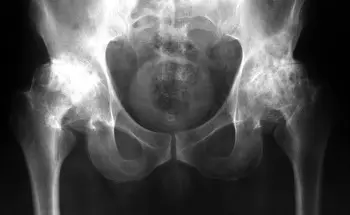

2 বছর আগে, আমি প্রথম আমার হাঁটু এবং নিতম্বে হালকা ব্যথা অনুভব করেছি। ব্যথা গুরুতর ছিল না, আমি এতে খুব বেশি মনোযোগ দিইনি... দেখা গেল, জয়েন্টের রোগগুলি খুব বিপজ্জনক, এবং আপনার এখনই তাদের সাথে লড়াই করা উচিত, আমার মতো দেরি করবেন না! একদিন, আমি আমার হাঁটুতে খুব বেশি তীব্র ব্যথা অনুভব করিনি, কিন্তু তীব্র ব্যথা অনুভব করেছি, এবং আমার নিতম্বের জয়েন্টেও ব্যথা শুরু হয়েছিল। আমি ভেবেছিলাম: কোনও ব্যাপার নয়, এটি নিজে থেকেই চলে যাবে, যেমনটি সাধারণত হয়। আমি কিছু ওষুধ, ক্যাপসুল কিনেছি এবং সেগুলি ব্যবহার শুরু করেছি। প্রায় এক সপ্তাহ ধরে আমি কষ্ট পাচ্ছিলাম, আমার অবস্থা তীব্রভাবে খারাপ হতে শুরু করে, ব্যথা অসহ্য হয়ে ওঠে, নিতম্বের জয়েন্টে তীব্র ব্যথা শুরু হয়, আমি প্রথমবারের মতো ডাক্তারের কাছে যাওয়ার সিদ্ধান্ত নিলাম।

কোর্সের পর, আমি সম্পূর্ণরূপে সুস্থ ছিল! আমি স্বাধীনভাবে হাঁটতে শুরু করেছি, কোনও কুঁচকানো বা ব্যথা ছিল না! আমার নিতম্ব এবং হাঁটুতে কখনও ব্যথা হয়নি বলে মনে হচ্ছে!!

এই ছবিগুলো দেখো। সঠিক ছবিতে, জয়েন্টের জায়গা নেই, হাড়গুলো একে অপরের সাথে ঘষছে, যার ফলে তীব্র ব্যথা হচ্ছে। আর এই প্রক্রিয়া বন্ধ করা খুব কঠিন! কয়েক বছরের মধ্যে, ব্যক্তিটি অক্ষম হয়ে যাবে এবং নিজের যত্ন নিতে পারবে না।

এই সবই তরুণাস্থি টিস্যুকে নরম করে, জীর্ণ করে এবং পাতলা করে। প্রতিটি নতুন নড়াচড়ার সাথে, তরুণাস্থি জীর্ণ হয়ে যায় এবং বিকৃত হয়ে যায়, হাড়গুলি একে অপরের সাথে ঘষতে শুরু করে, যার ফলে অসহনীয় ব্যথা হয়।